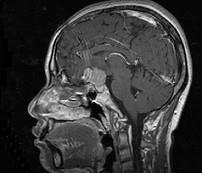

问题 女,32岁,右眼视物模糊1年,加重2月,请根据所提供图像,选择最可能的诊断()

选项 A.鞍区脑膜瘤 B.鞍区垂体瘤 C.鞍区转移瘤 D.鞍区海绵状血管瘤 E.鞍区动脉瘤

答案 A